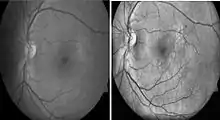

Diabetic retinopathy

Diabetic retinopathy is a disease of the retina that is diagnosed predominantly by fundoscopic images. Diabetic patients in industrialised countries generally undergo regular screening for the condition. Imaging is used to recognize early signs of abnormal retinal blood vessels. Manual analysis of these images can be time-consuming and unreliable.[75][76] CAD has been employed to enhance the accuracy, sensitivity, and specificity of automated detection method. The use of some CAD systems to replace human graders can be safe and cost effective.[76]

Histogram Equalization Sample Image. Left: Normal gray-scale fundoscopic image. Right: Post-histogram equalization processing.[79]